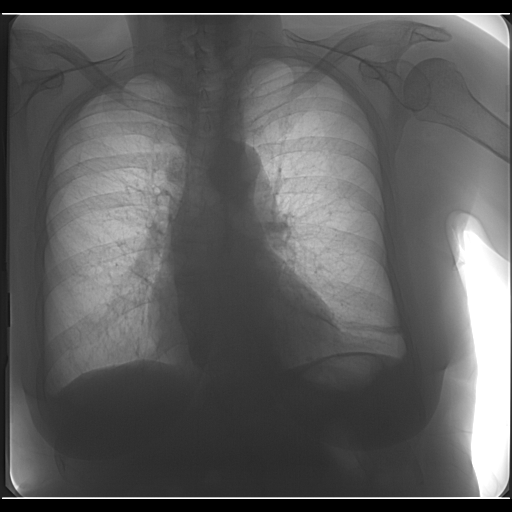

Есть ли на прилагаемых ФЛГ гемоторакс (5 день после перелома 7,8,9 ребер) Прикрепленные файлы

Anton   Нет.   10.01.2018 - 19:03

Не вижу.   10.01.2018 - 21:11

Радомир   Нет гемоторакса. Снимки высокого качества. Позволя...   11.01.2018 - 01:27![]() ![]()  |